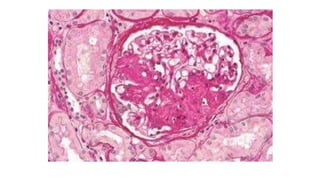

Normal Kidney Glomerulus Diabetic Glomerulosclerosis (the main cause of

nephrotic syndrome in adults)

Diabetic Glomerulonephritis (in a

patient with nephrotic syndrome)

Normal Kidney GlomerulusDiabetic Glomerulosclerosis (the main cause of nephrotic syndrome in adults) Diabetic Glomerulonephritis (in a patient with nephrotic syndrome)